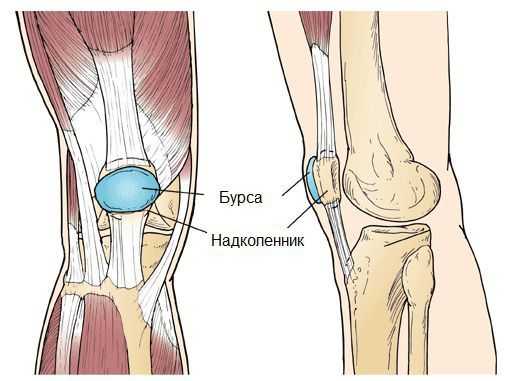

Синовиальная сумка (или бурса) — это небольшая полость с жидкостью. Бурсы расположены в местах наибольшего трения различных тканей: сухожилий, мышц и костных выступов. Благодаря нормальному функционированию суставных сумок, трение при движении уменьшается. Стенка бурс двухслойная: наружный слой состоит из плотной соединительной ткани; внутренний называется синовиальной оболочкой, в норме он вырабатывает небольшое количество жидкости. При нарушении работы синовиальных сумок движения сустава невозможны.

Коленный сустав — один из наиболее сложных суставов в теле человека. Он имеет в своём составе большое количество синовиальных сумок:

- наднадколенниковая (супрапателлярная);

- преднадколенниковая (препателлярная);

- поднадколенниковые поверхностная и глубокая (инфрапателярные);

- сумка гусиной лапки (анзериновая);

- сумка медиальной (внутренней) боковой связки;

- сумка латеральной (наружной) боковой связки;

- сумка илиотибиального тракта;

- сумка сухожилия полуперепончатой мышцы (полуперепончатая);

- сумка медиальной (внутренней) головки икроножной мышцы — икроножная сумка;

- сумка подколенной мышцы — подколенная.

Бурсит может возникнуть в любой из этих видов сумок [10] .

Киста Бейкера – это воспаление синовиальной оболочки капсулы коленного сустава. По своей сути – это воспаление синовиальной оболочки сустава (артрит). При артрите суставная жидкость продуцируется в избыточном количестве. При артрите коленного сустава синтез суставной (синовиальной) жидкости более интенсивный, чем ее всасывание. Жидкость накапливается в суставе, заполняя все карманы капсулы сустава. Когда накапливается много синовиальной жидкости, происходит заполнение в том числе задних карманов капсулы (красные стрелки).

Для лучшего представления о капсуле сустава, внизу приведена иллюстрация из анатомического учебника, которая демонстрирует, насколько сложна объемная капсула сустава и какую она имеет конфигурацию: показаны передний заворот и частично задний.

Каста Бейкера становится видна с момента, когда жидкостью заполняется задний заворот капсулы. В этом случае он легко пальпируется в подколенной ямке (по задней поверхности коленного сустава).